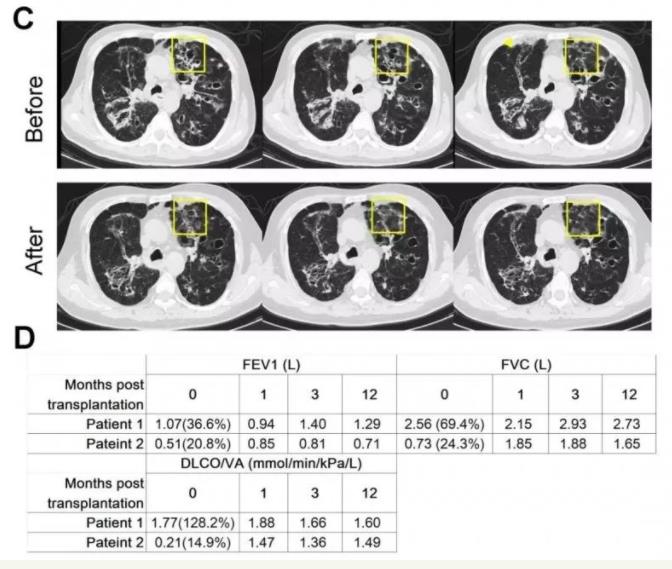

《蛋白質(zhì)與細(xì)胞》雜志以封面文章形式發(fā)表了同濟(jì)大學(xué)醫(yī)學(xué)院左為教授團(tuán)隊(duì)重大突破成果??蒲腥藛T從患者支氣管取出干細(xì)胞,體外擴(kuò)增后移植至患者肺部病灶部位;3至6個(gè)月后,這些干細(xì)胞形成了新的肺泡和支氣管結(jié)構(gòu),完成了對(duì)患者肺部損傷組織的修復(fù)替代。

目前左為團(tuán)隊(duì)一共開展了超過80例臨床肺干細(xì)胞移植,這些患者的肺功能,特別是肺的彌散功能有比較明顯的改善。

▲ 肺功能檢測(cè)提示,移植干細(xì)胞三個(gè)月之后各項(xiàng)肺功能開始出現(xiàn)好轉(zhuǎn)并保持到一年之后